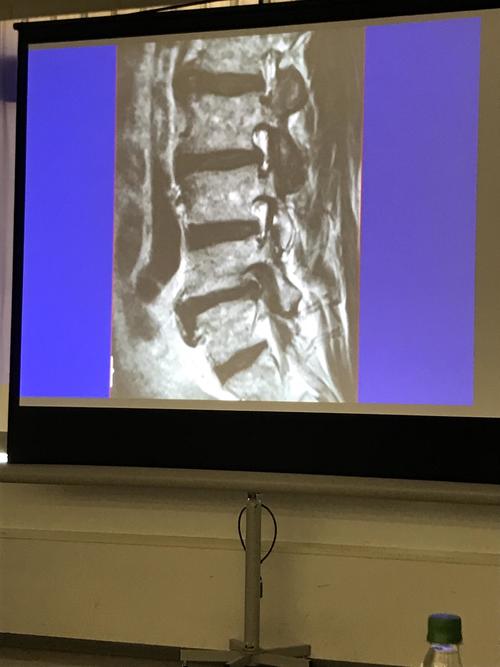

腰椎椎間板ヘルニア.JPG

昨日は「小児の骨端症」